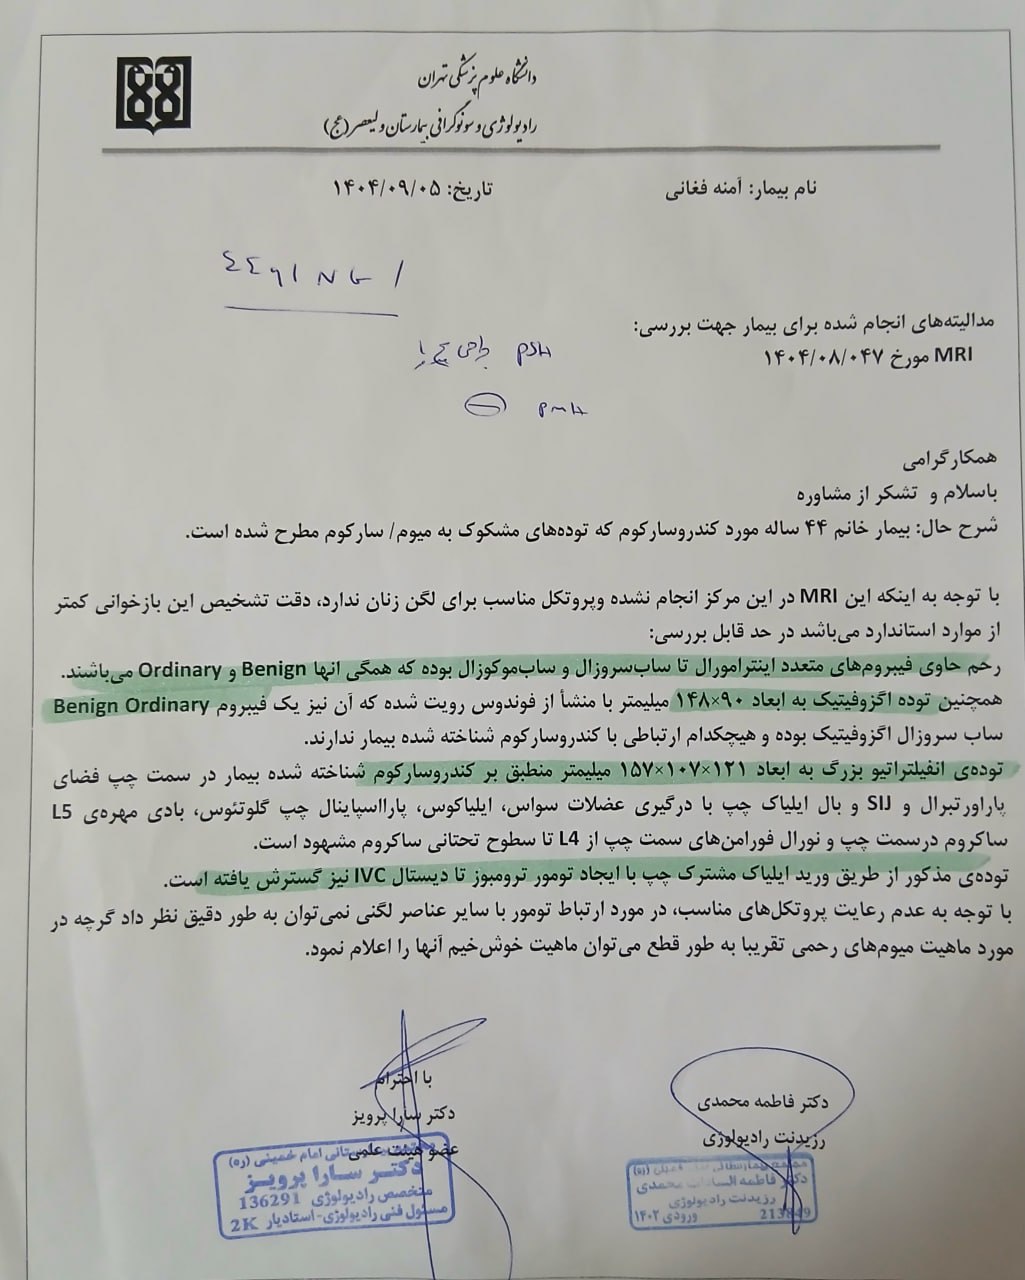

در بررسیهای تصویربرداری (MRI)،در تاریخ 24.7 ، تودهای با تشخیص کندروسارکوما همراه با DVT گزارش شده است. بیمار سابقه درد لگن داشته که شدت آن در حال حاضر نسبت به گذشته کاهش یافته است. به گفته بیمار، حجم توده در ابتدا در حدود اندازه یک تخممرغ بوده که در حال حاضر کاهش یافته است. همچنین تورم اندام تحتانی در حال حاضر نسبت به قبل کمتر شده است.

مراجعه کرده است. پس از بررسی های انجام شده در MRI انجام شده توده با درگیری مفصل ساکروایلیاک چپ و DVT؛ ابتدا تحت درمان DVT قرار گرفته است و سپس جهت پیگیری تومور رویت شده تحت بیوپسی قرار گرفته است و با تشخیص کندروسارکوما به این مرکز مراجعه کرده است و تحت کموتراپی و رادیوتراپی قرار گرفته و سایز تومور کاهش یافته است.

(تصویر مربوط به این مراجعه نیست) Other:

(تصویر مربوط به این مراجعه نیست) Other:

(تصویر مربوط به این مراجعه نیست) Other:

(تصویر مربوط به این مراجعه نیست) Other:

(تصویر مربوط به این مراجعه نیست) Other:

(تصویر مربوط به این مراجعه نیست) Other:

(تصویر مربوط به این مراجعه نیست) Other:

(تصویر مربوط به این مراجعه نیست) Other:

(تصویر مربوط به این مراجعه نیست) Other:

(تصویر مربوط به این مراجعه نیست) Other:

(تصویر مربوط به این مراجعه نیست) Other:

(تصویر مربوط به این مراجعه نیست) Other:

(تصویر مربوط به این مراجعه نیست) Other:

(تصویر مربوط به این مراجعه نیست) Other:

(تصویر مربوط به این مراجعه نیست) Other:

(تصویر مربوط به این مراجعه نیست) Other:

(تصویر مربوط به این مراجعه نیست) Other:

(تصویر مربوط به این مراجعه نیست) Other:

(تصویر مربوط به این مراجعه نیست) Other:

(تصویر مربوط به این مراجعه نیست) Other:

(تصویر مربوط به این مراجعه نیست) Other:

(تصویر مربوط به این مراجعه نیست) Other:

(تصویر مربوط به این مراجعه نیست) Other:

(تصویر مربوط به این مراجعه نیست) Other:

(تصویر مربوط به این مراجعه نیست) Other:

(تصویر مربوط به این مراجعه نیست) Other:

(تصویر مربوط به این مراجعه نیست) Other:

(تصویر مربوط به این مراجعه نیست) Other:

(تصویر مربوط به این مراجعه نیست) Other:

(تصویر مربوط به این مراجعه نیست) Other:

(تصویر مربوط به این مراجعه نیست) Other:

(تصویر مربوط به این مراجعه نیست) Other:

(تصویر مربوط به این مراجعه نیست) Other:

(تصویر مربوط به این مراجعه نیست) Other:

(تصویر مربوط به این مراجعه نیست) Other:

(تصویر مربوط به این مراجعه نیست) Other:

(تصویر مربوط به این مراجعه نیست) Other:

(تصویر مربوط به این مراجعه نیست) Other:

(تصویر مربوط به این مراجعه نیست) Other:

(تصویر مربوط به این مراجعه نیست) Other:

(تصویر مربوط به این مراجعه نیست) Other:

(تصویر مربوط به این مراجعه نیست) Other:

(تصویر مربوط به این مراجعه نیست) Other:

(تصویر مربوط به این مراجعه نیست) Other:

(تصویر مربوط به این مراجعه نیست) Other:

(تصویر مربوط به این مراجعه نیست) Other:

(تصویر مربوط به این مراجعه نیست) Other: